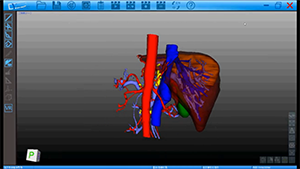

术中影像引导的肝S7、8段定构切除治疗结肠癌肝转移

作者:王勋 | 作者单位:解放军总医院第一医学中心

发布时间:2020-09-03 21:37:33